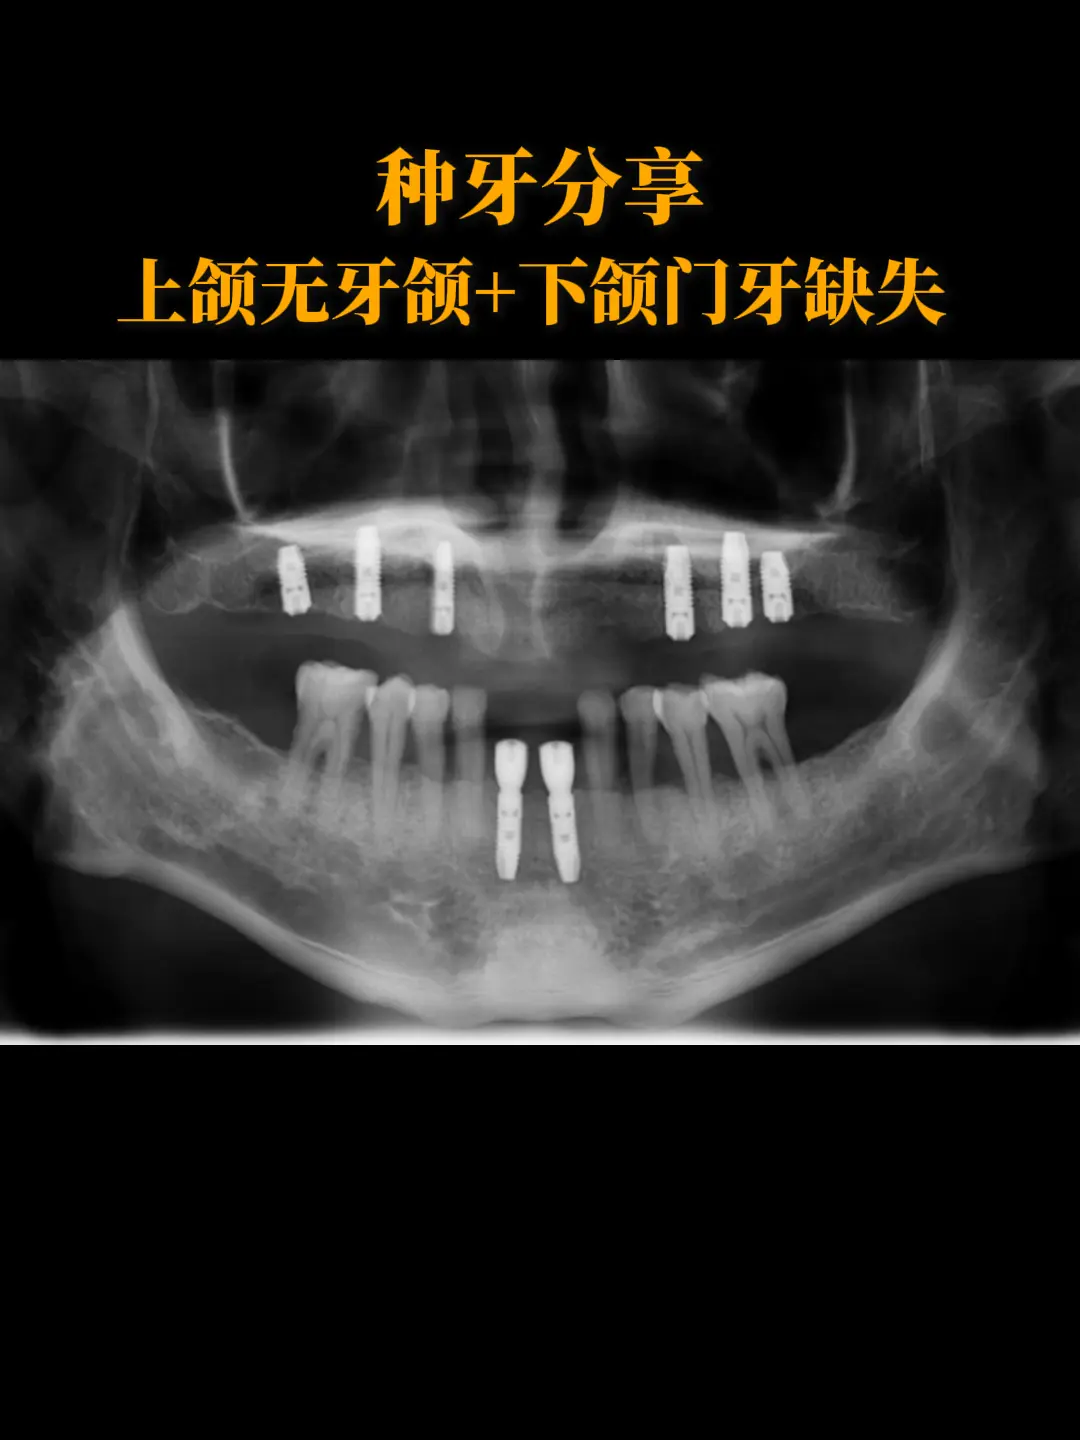

【种牙分享】上颌无牙颌+下颌门牙缺失。这是一位41岁男性患者,他的上下颌牙齿因松动逐渐于外院拔除,曾于外院行活动义齿修复,诉使用不便,咨询种植修复。检查后,牙槽骨满足种牙条件,就在上颌植入6颗种植体,下颌植入2颗种植体,完成全口牙齿修复。